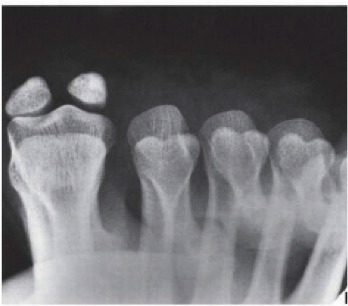

Sesamoid injury

• Classification

• medial/tibial sesamoid

• more common

• attaches to adductor hallucis

• lateral/fibular sesamoid

• attaches to abductor hallucis

• Recommended views

• AP

• lateral

• tangential

• lewis

• causton

• Findings

• proximal migration of sesamoids

• be suspicious of intrinsic minus hallux